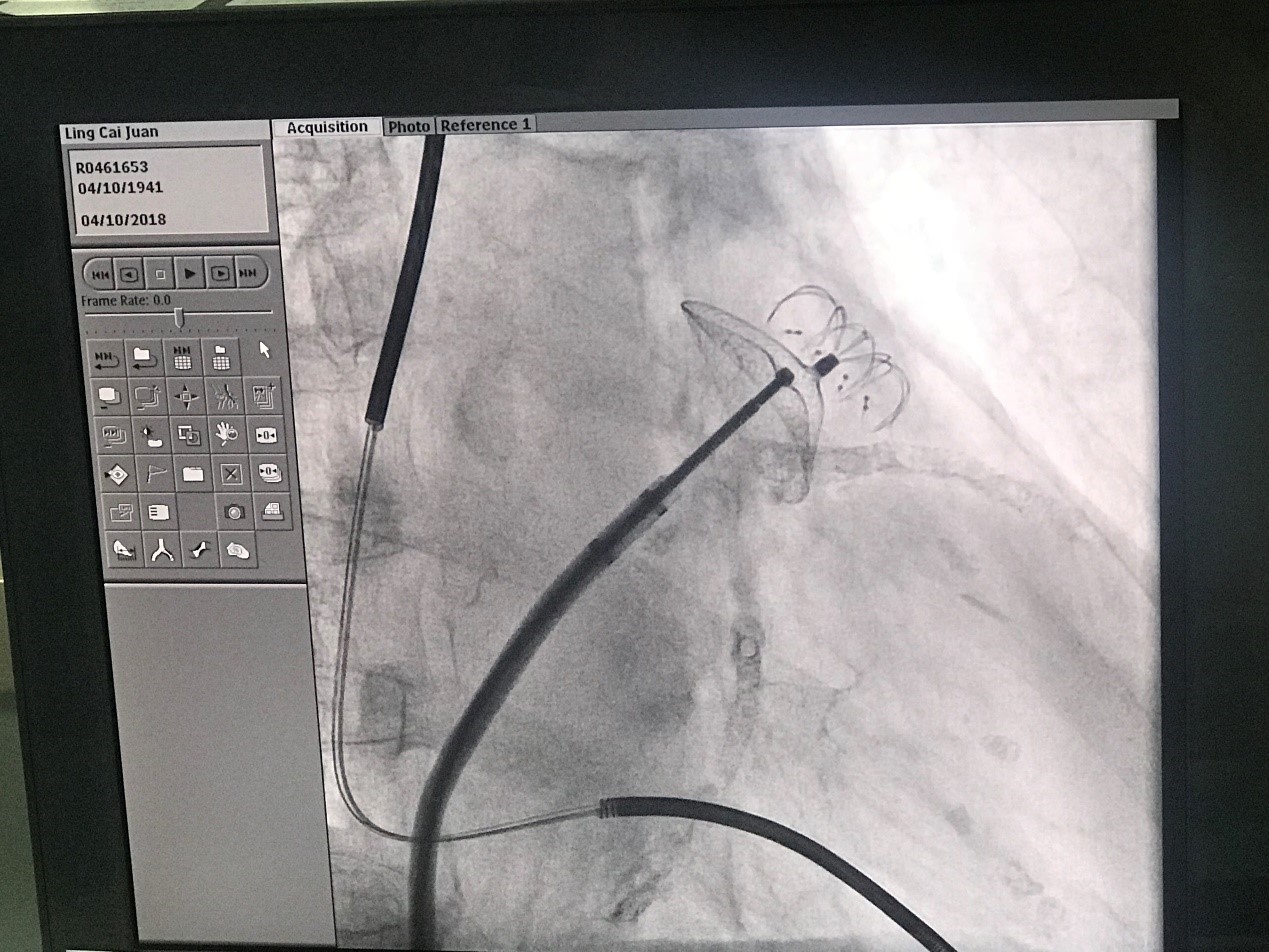

该例手术由深圳市罗湖区人民医院心内科裴晓阳教授和来自香港的林逸贤教授共同担任术者,接受手术的患者为一名77岁女性,体重45公斤,被诊断为心房颤动,已放置两根冠脉支架和一个心脏起搏器。房间隔穿刺后经DSA造影测量患者左心耳开口直径为31.06mm,锚定区直径约为20.79mm,左心耳形态类似风袋型。裴晓阳教授和林逸贤教授选用型号为LT-LAA-2234、独特小伞大盘设计的LAmbre™左心耳封堵器对患者实施封堵。手术全程未使用食道超声,未进行全麻,仅利用气管插管静脉复合麻醉对患者进行少量麻醉处理。患者在术中可以和医生顺畅交流,导管室内气氛轻松,完全没有手术的紧张感,且将手术时间进一步缩短到30分钟以内。

(图:术中造影)

(图:LAmbre™左心耳封堵器植入后造影)